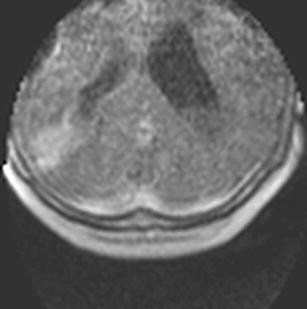

We performed an iMRI-guided surgical procedure in a patient with a cystic lesion of the inferior parieto-occipital lobe while the patient was placed in a semi-sitting position, employing a mobile 0.15-T intraoperative MRI system. For that purpose, we adapted a standard OR table according to the needs of iMRI.

Patient positioning could be accomplished easily. For intraoperative scanning, the OR table was tilted backwards so as to position the patient’s head in the magnet’s aperture. Obtained images were used for neuronavigated cyst evacuation via burr hole trephination after repositioning the OR table. Subsequent intraoperative imaging documented collapse of the cyst at the end of the procedure. There were no adverse effects resulting from the combination of semi-sitting position and iMRI guidance.